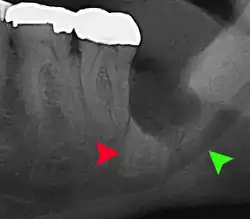

| 3D CT of an impacted wisdom tooth adjacent the inferior alveolar nerve prior to removal of wisdom tooth | |

| Diagnostic method | Examination, x-ray |

If the tooth cannot be assessed with clinical exam alone, the diagnosis is made using either a panoramic radiograph or cone-beam CT. Where unerupted wisdom teeth still have eruption potential several predictors are used to determine the chance of the teeth becoming impacted. The ratio of space between the tooth crown length and the amount of space available, the angle of the teeth compared to the other teeth are the two most commonly used predictors, with the space ratio being the most accurate. Despite the capacity for movement into early adulthood, the likelihood that the tooth will become impacted can be predicted when the ratio of space available to the length of the crown of the tooth is under 1.[5]: 141

Long-term complications can include periodontal complications such as bone loss on the second molar following wisdom teeth removal. Bone loss as a complication after wisdom teeth removal is uncommon in the young but present in 43% of those of 25 years of age or older.[23] Injury to the inferior alveolar nerve resulting in numbness or partial numbness of the lower lip and chin has reported rates that vary widely from 0.04% to 5%.[23] The largest study is from a survey of 535 oral and maxillofacial surgeons in California, where a rate of 1:2,500 was reported.[26]

Coronectomy is a procedure where the crown of the impacted wisdom tooth is removed, but the roots are intentionally left in place. It is indicated when there is no disease of the dental pulp or infection around the crown of the tooth, and there is a high risk of inferior alveolar nerve injury.[32]